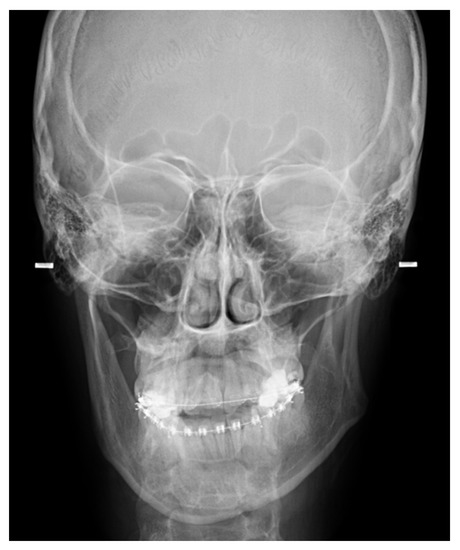

- A condylectomy with BSSO and Lefort I simultaneously was described by Wolford in 2002; however, some authors report operated TMJ joint instability, which might be related to the degree of excised bone and poor condyle stabilization with at least lateral pterygoid muscle reattachment or other, perhaps even related with IMF intramaxillary fixation devices to stabilize the occlusion [75] (Figure 9);

- (7)